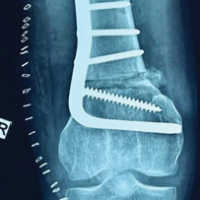

Fracture was reduced temporarily with a bone reduction clamp. Plate was planned to be fixed above the clavicle at a desirable distance of 4 cm in our case to accommodate dressing. Plate was positioned anterosuperiorly for patient’s ergonomic comfort. An 8 holed left clavicle LCP was used as an external fixator. Plate is held close to the bone initially, locking sleeve was attached and pilot hole is drilled with a 2.8 mm drill bit. Depth gauge was used to determine the length of pilot hole. Appropriate screw length can be calculated by adding 3 cm (which was the distance between the plate and skin) to the measured depth of pilot hole. For example, if 14 mm is the depth of pilot hole, adding 3 cm gives a screw length of 44 mm. Screws were inserted through the locking hole into the pre-drilled pilot hole until it engaged the far cortex. The plate was then lifted up and secured in an appropriate position before continuing to drive the screw heads into the locking holes. 3.5 mm cortical screws with bicortical purchase of determined length were inserted and locked to the plate. Inferiorly, a bone lever is used to provide counter force and protect vascular structures while drilling. Screws to be ideally placed in a near-near far-far position according to the principle of external fixation. Similarly, a total of 2 locking screws on either side of fracture are applied (Fig. 3).

Figure 3: Intraoperative and C-arm image of clavicle locking compression plate used as ex-fix.